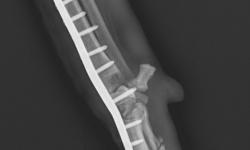

Pacient č.: 2. - pooperační rtg.